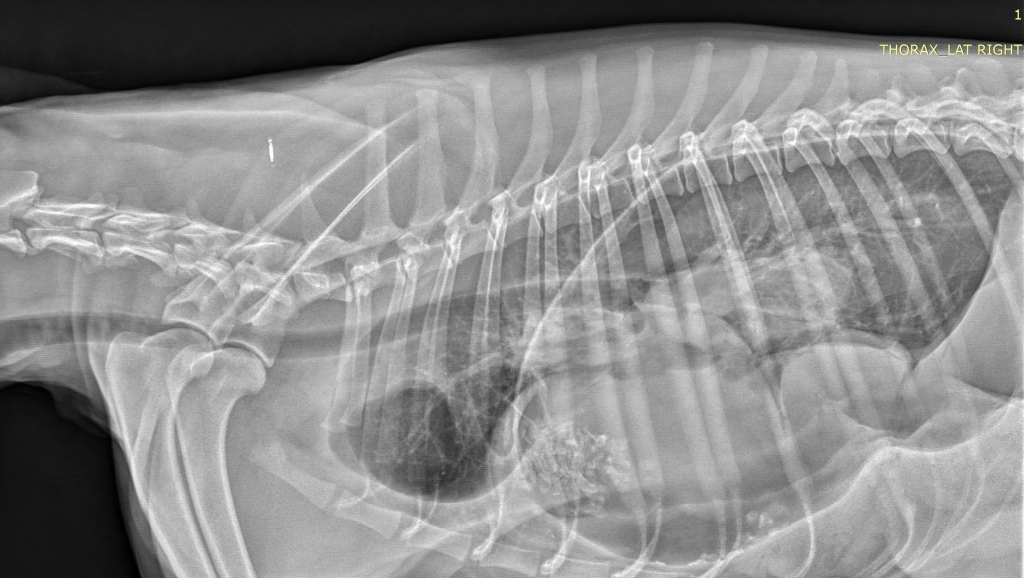

Dr Henry L’Eplattenier, clinical director at Southfields, arranged for radiographs of Florence’s chest to be taken and soon discovered why the pup was in such a poorly condition – her stomach and part of her liver were actually sitting in her chest cavity and compressing her lungs. He then had to carry out an emergency operation to save her life.

“Radiographs showed she had a very dilated stomach which was compressing the lungs and preventing proper ventilation of the lungs.

“The outline of the diaphragm (the line separating the abdomen from the chest) could not be recognised either, which suggested a rupture of the diaphragm.